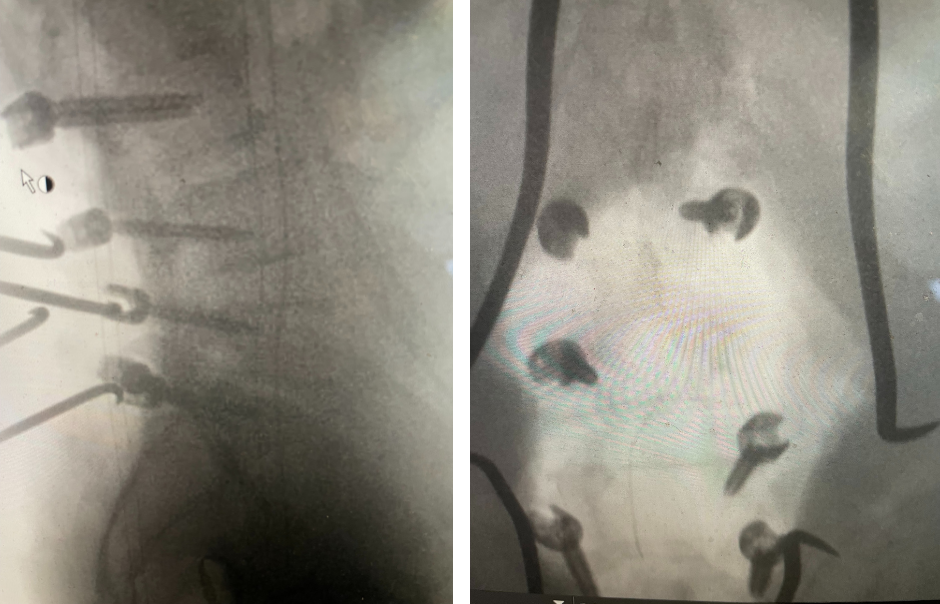

Figure 3. AP and lateral intraoperative fluoroscopic images demonstrating balanced pedicle screw placement.

We decided to perform a lumbar decompression L2-S1 with an instrumented fusion. The patient intraoperatively had severe thecal sac compression with severe facet arthropathy and thickened ligamentum flavum. The patient had bilateral L5 pars defects with a floating L5 lamina. Because of these factors and the patient’s age, it was decided to place screws (Fig. 3).  The patient did well postoperatively with relief of his lower extremity pain and weakness.